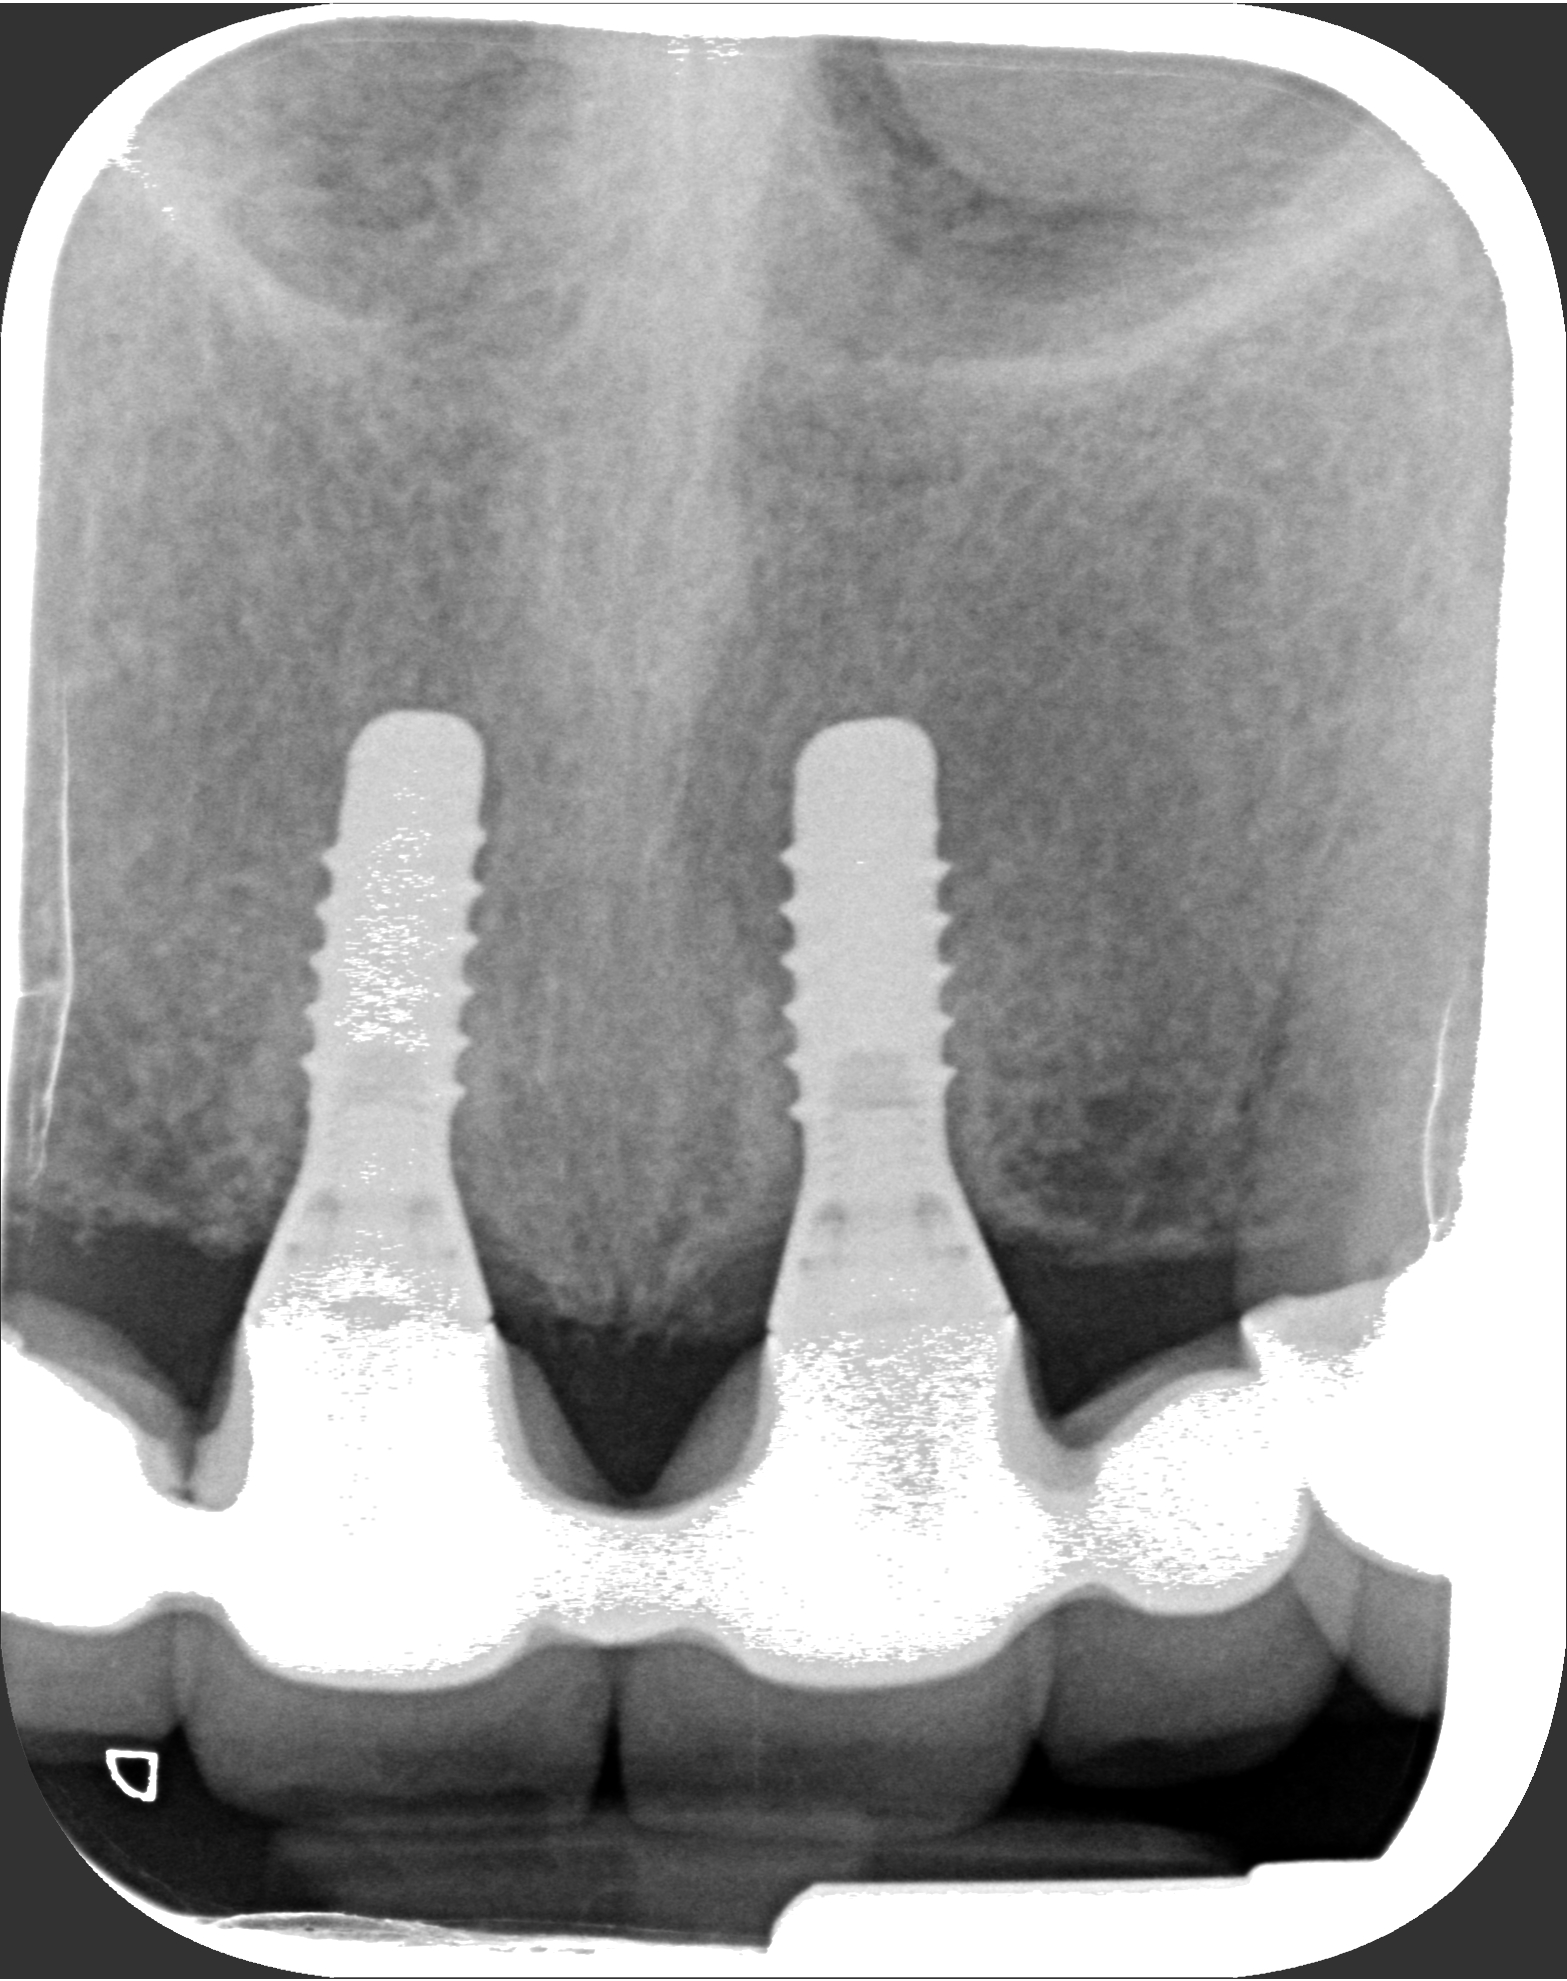

6. Εμφυτεύματα στην πρόσθια περιοχή (αισθητική ζώνη)

Στην ασθενή οι τομείς στην άνω γνάθο είχαν χαθεί λόγω τερηδόνας. Στην περιοχή τοποθετήθηκαν δύο εμφυτεύματα και έγινε μία γέφυρα τεσσάρων τεμαχίων (δοντιών) επί αυτών.

Η κλινική εικόνα μετά την τελική αποκατάσταση (γέφυρα) κρίνεται απόλυτα επιτυχής.

Εμφυτεύματα στην πρόσθια περιοχή (αισθητική ζώνη)

Τελική Ακτινογραφία